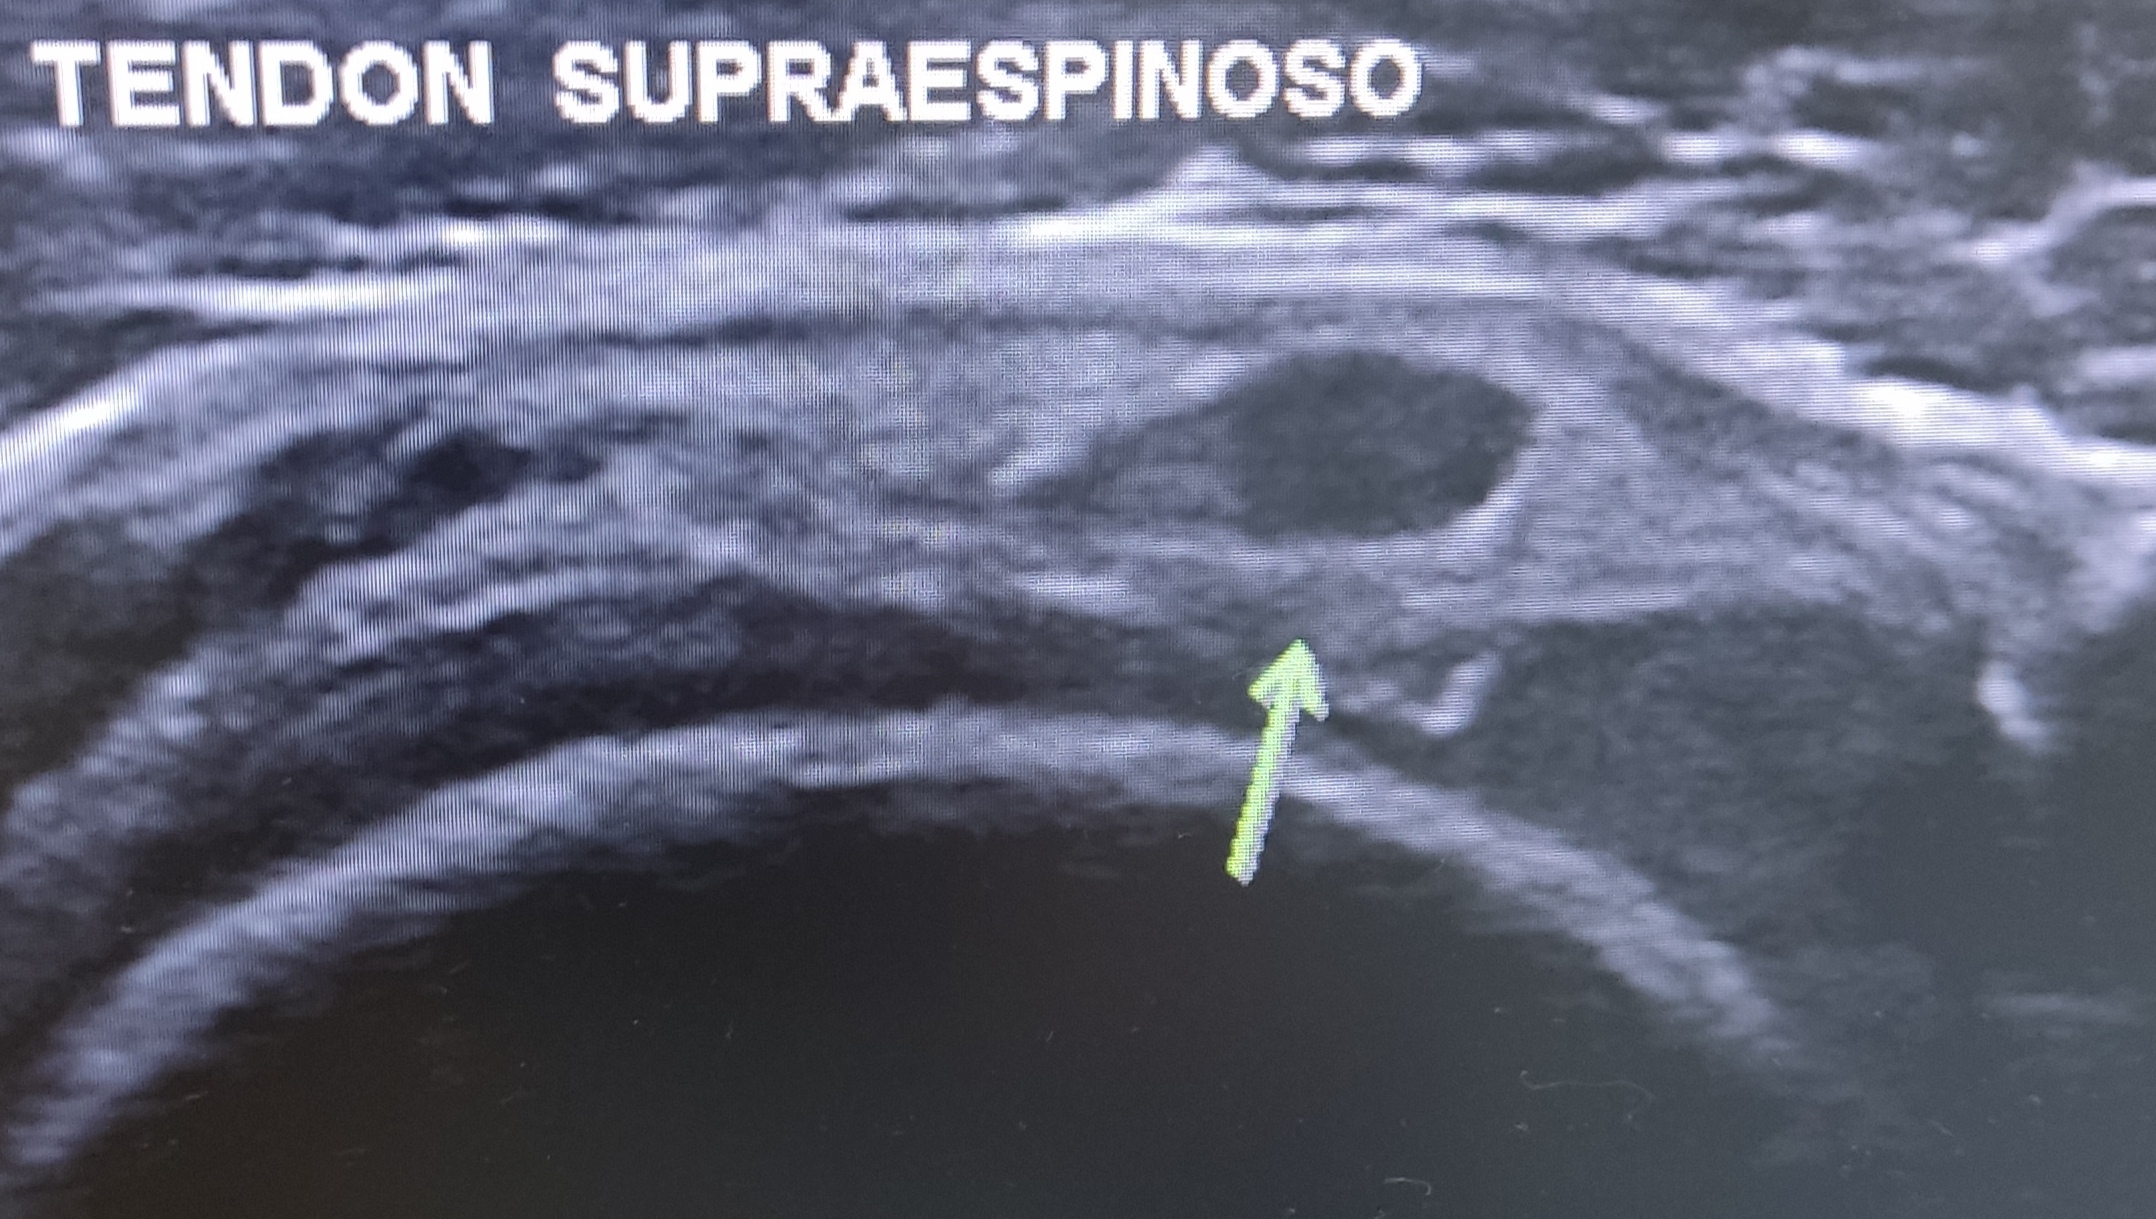

En el corte transversal del supraespinoso se observan varias imágenes hipoecoicas bien delimitadas en el espesor del tendón que podrían hacer sospechar una rotura parcial intrasustancia.

En el corte transversal del supraespinoso se observan varias imágenes hipoecoicas bien delimitadas en el espesor del tendón que podrían hacer sospechar una rotura parcial intrasustancia o podrían corresponder con una persistencia de fibras musculares del supraespinoso más allá del arco óseo acromial (lo que puede ser bastante frecuente en gente joven menor de 50 años). Podemos "tirarnos a la piscina" y sugerir que tiene un supraespinoso que distalmente al acromión/ligamento coracoacromial está formado por fibras tendinosas en su mayoría, acompañadas por zonas de fibras musculares que con el envejecimiento se irán fibrosando, convirtiéndose en fibras tendinosas.